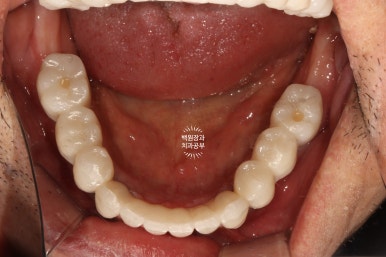

씹는면에서 본 임시치아입니다.

이제 제법 치아의 모양을 갖췄네요. 여기까지 오는데 7개월이라는 시간이 걸렸습니다.

그리하여 완성된 최종보철물입니다!!

옛날부터 임플란트 틀니용으로 사용하시던 임플란트 3개는 임플란트 주위염이 조금 있어 약~간 쇠기둥 색깔이 보인다는 단점이 있긴 하지만, 다른 임플란트들은 꽤나 예쁘게 제작이 되었네요.

위 아래 교합면 사진을 보시면, 과연 이게 임플란트인가? 싶으실거에요. 치아에 지르코니아 크라운을 붙인 것과 큰 차이를 못느낄 정도로 정말 자기 치아같이 예쁘게 제작된 임플란트 크라운을 보실 수 있습니다!!